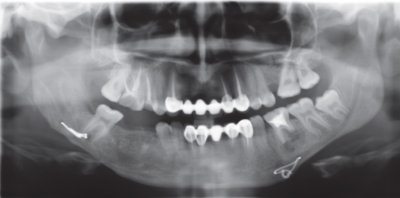

При внутриротовом доступе разрез проводили по переходной складке или альвеолярному гребню и минипластины устанавливали по основанию альвеолярной части нижней челюсти (рис. 5) или по вершине альвеолярного гребня при остеосинтезе в области угла нижней челюсти.

Рис. 5. Ортопантомограмма. Больной В., 78 лет